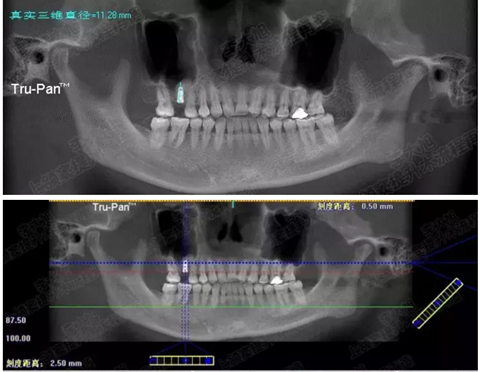

病例一

上頜竇多分隔3mm

05.png

提升8mm

06.png

07.png

修復(fù)時(shí)根尖片

08.png

09.png